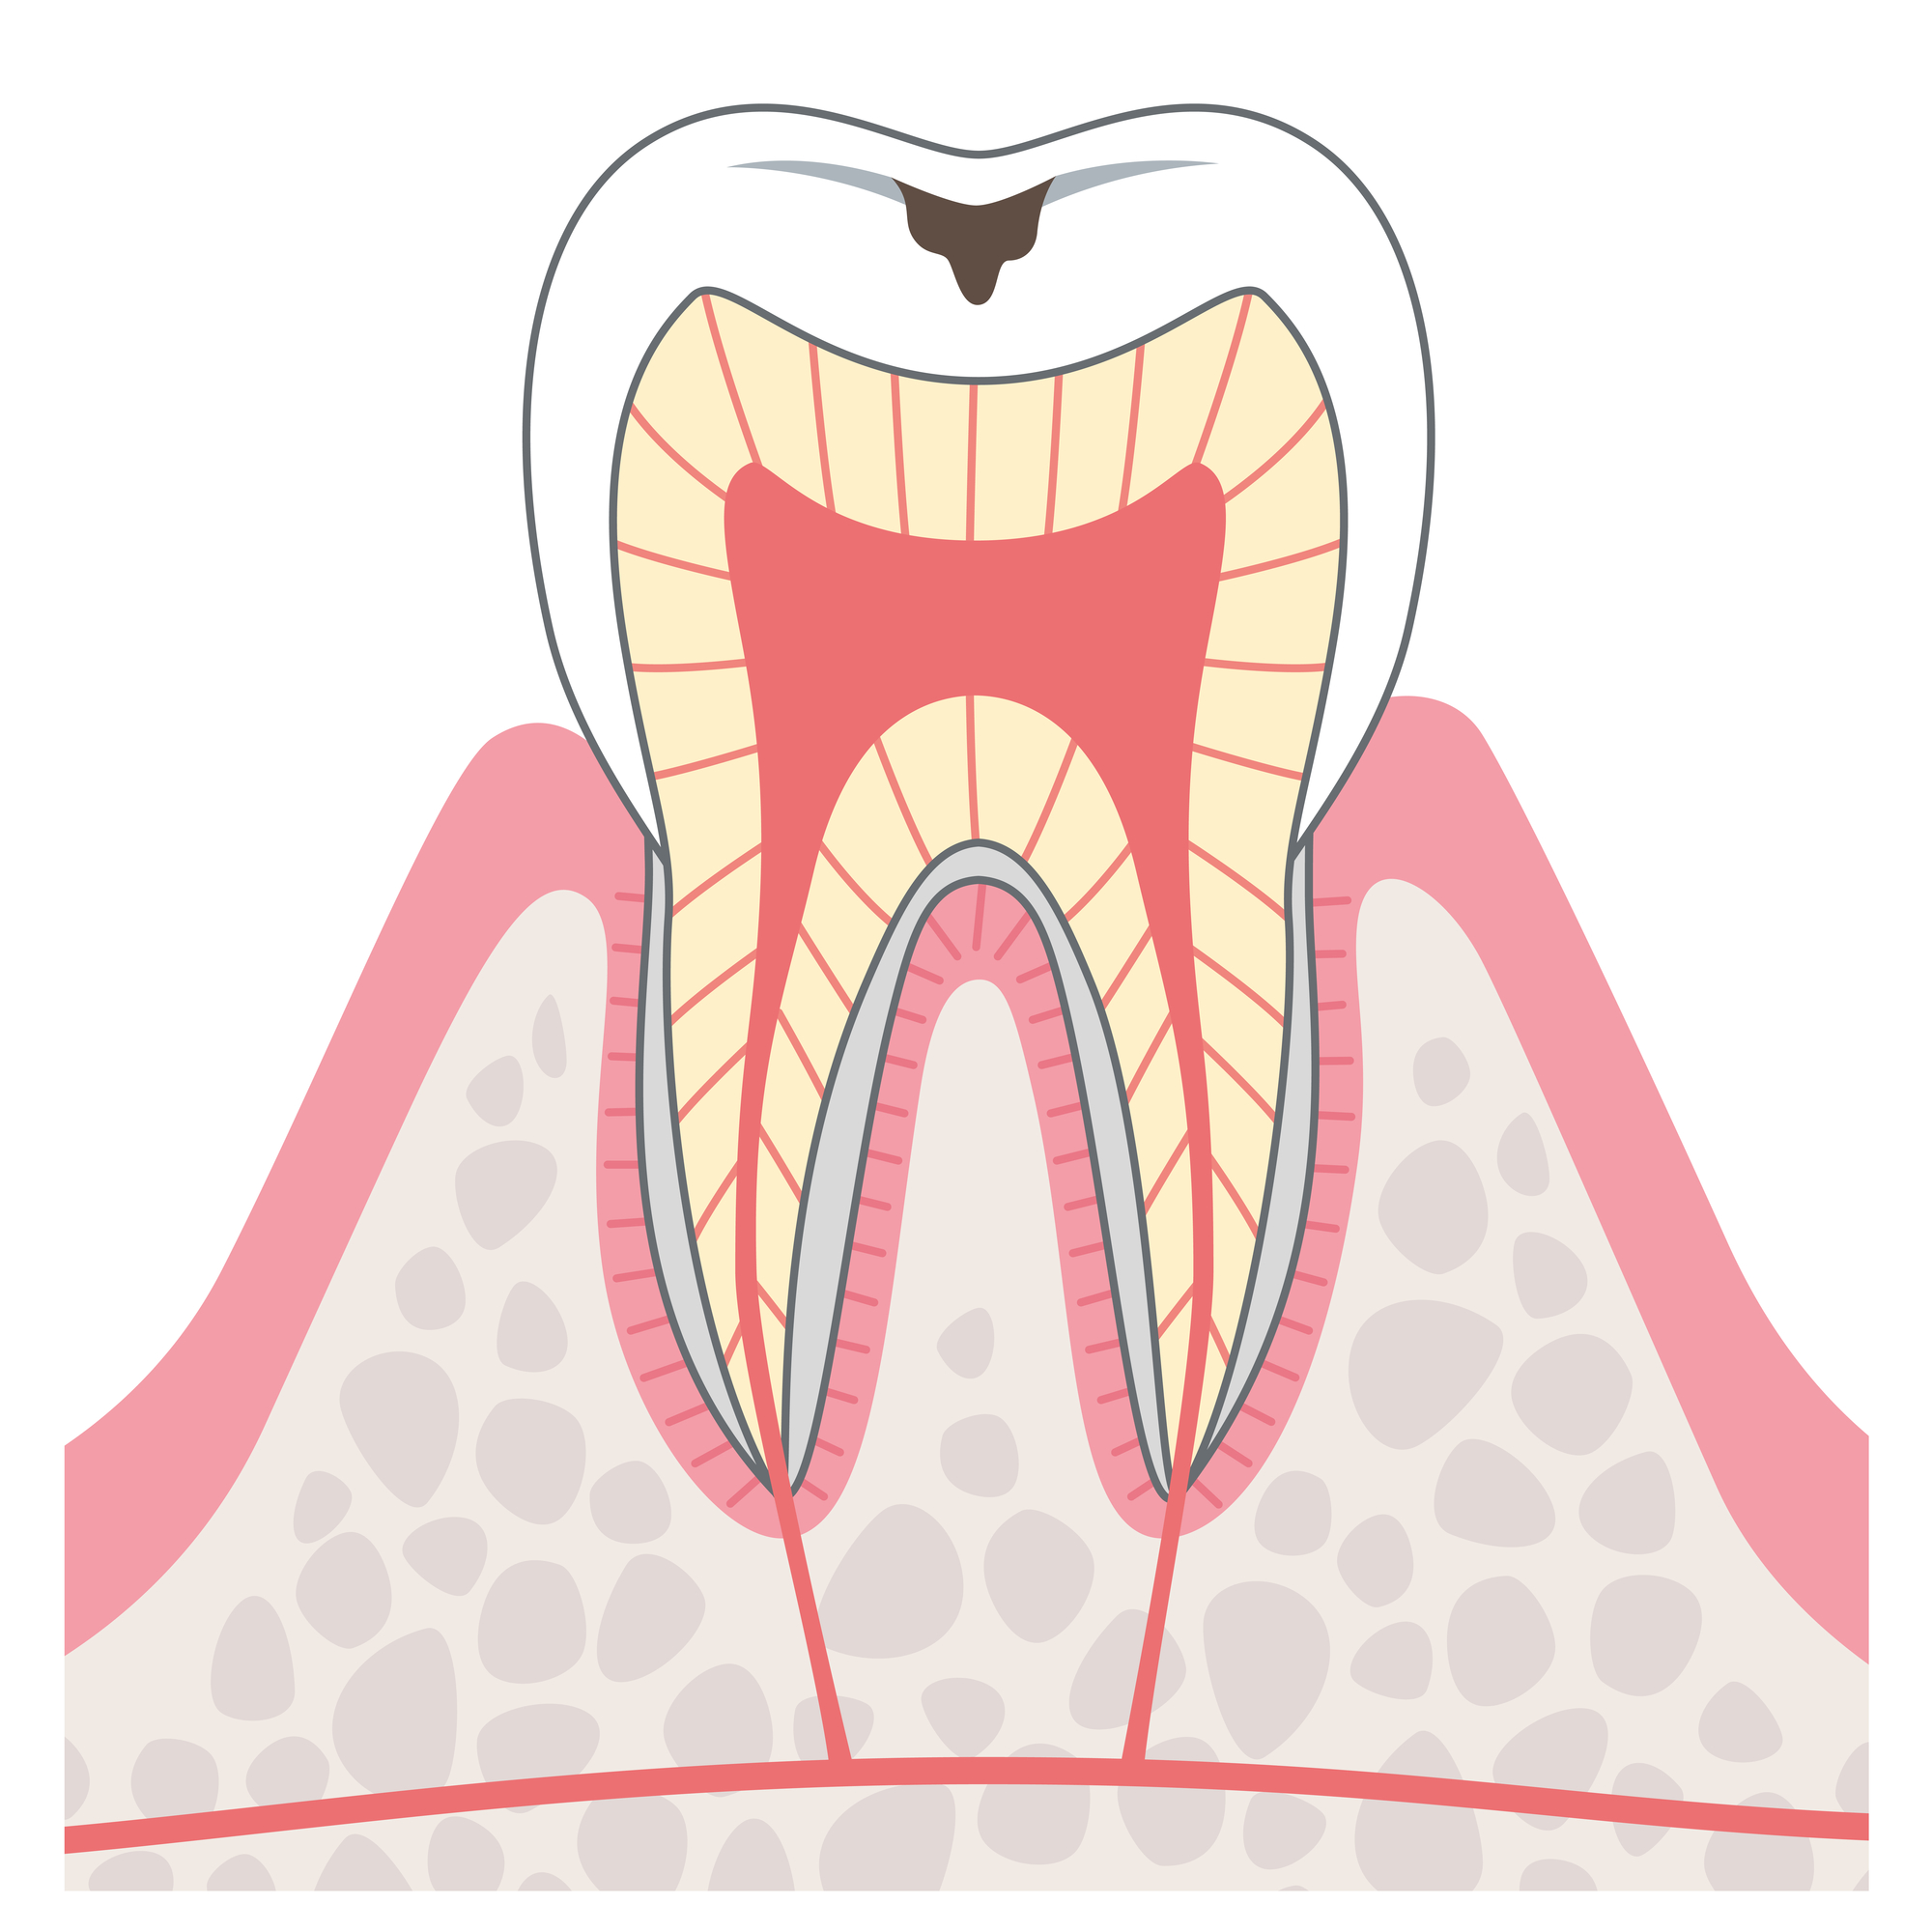

C1

C1の段階では、むし歯菌がエナメル質を溶かします。痛みはありません。

この段階で治療をできると理想的です。

治療方法

- 詰め物